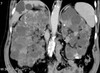

Autosomal dominant polycystic kidney disease ## Footnote CT of the abdomen (coronal reformats) demonstrates both kidneys to be markedly enlarged by innumerable cysts ranging in size from a few millimetres to multiple centimetres. These cysts also vary in density: most are near-water density, some are hyperdense, others are calcified. Also present are numerous cysts in the liver. The pancreas is unremarkable. Features are consistent with autosomal dominant polycystic kidney disease, which was subsequently confirmed.

Sigmoid volvulus ## Footnote dilation causes the classic coffee-bean sign, a pathognomonic of sigmoid volvulus.

Polycystic kidney disease

Autosomal Dominant Polycystic Kidney Disease